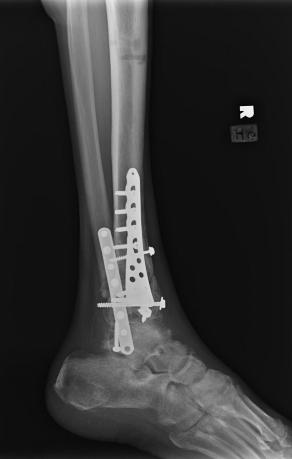

Post-corrective surgery X-Rays of the damaged right & left legs / ankles

The first two x-rays show Liam’s left ankle and pelvis prior to the accident. For comparison purposes it is interesting to see the

differences. The next x-rays were taken after the corrective surgery performed by Dr. Armendariz. Noticed that Dr. Armendariz has used tibia

bracing and also aligned the bone fragments of the left leg so that they could heal in the proper orientation. The external fixation has been

removed and Liam’s left foot has been returned to a more natural alignment.